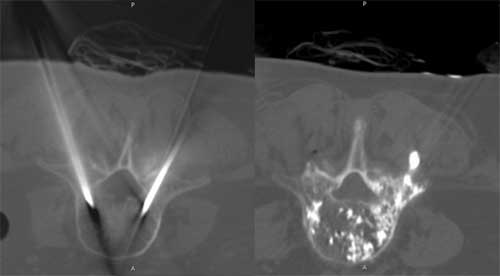

CT - důležité při postižení axiálního (osového) skeletu, stanovení stability, porušení kontinuity zadních elementů páteře

Cementoplastika - do osteolytické léze je perkutánní technikou aplikován kostní cement. Kontraindikací je vyplnění léze, která zasahuje do kloubu nebo intervertebrálního disku.

Cementoplastika může výhodně navazovat na předcházející RFA - provedení stabilizace osteolytické léze.

Vertebroplastika - podstatou metody je vyplnění obratlového těla (infiltrace) speciálním kostním cementem.

Kyphoplastika - metoda je obdobná jako vertebroplastika, ale před aplikací kostního cementu je pomocí speciálního nástroje vytvořená kavita (dutinka) v obratlovém těle nebo v osteolytickém ložisku. Tím může dojít k reparaci výšky obratlového těla. Při zavedení do osteolytické léze tato provedená komprese vytvoří tlakový uzávěr odvodných žil. Druhou výhodou je, že aplikovaný kostní cement není tekutý, má konzistenci "žvýkací gumy", a proto jen minimálně může dojít k úniku kostního cementu mimo oblast zájmu.